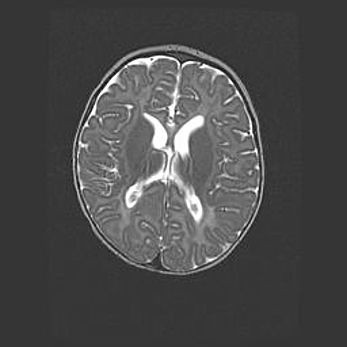

Лейкомаляция с кистозно-глиозной дегенерацией головного мозга.

Возраст: 2 месяца 25 дней

Вес: 6400 г

Окружность головы: 40 см

Срок гестации: 41 неделя

Лейкомаляцию относят к ишемически-гипоксическим повреждениям головного мозга, диагностируемым у новорожденных. При лейкомаляции в головном мозге обнаруживают очаги некроза, возникшие после тяжелой гипоксии и нарушения кровотока. В процессе морфогенеза очаги проходят три стадии: 1) развития некроза, 2) резорбции и 3) формирования глиозного рубца или кисты. Перивентрикулярная лейкомаляция (ПЛ) встречается примерно в 12% случаев среди новорожденных, обычно – у недоношенных детей, причем, частота ее зависит от массы, с которой младенец появился на свет. Наибольшее число малышей страдает лейкомаляцией, если масса при рождении 1500-2500 г.